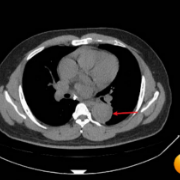

图说:胸部CT平扫纵隔窗提示胸主动脉增宽,管腔内弧形低密度影。

入院后监测显示,赵先生血压高达180/120mmHg(右侧)、180/116mmHg(左侧)。尽管患者并无明显胸闷、胸痛等典型症状,医护人员仍迅速完善胸部CT等相关检查。放射科主任张诗颖通过影像学表现进行专业判读,提示高度疑似主动脉夹层,相关结果立即引起医护团队的高度警觉。